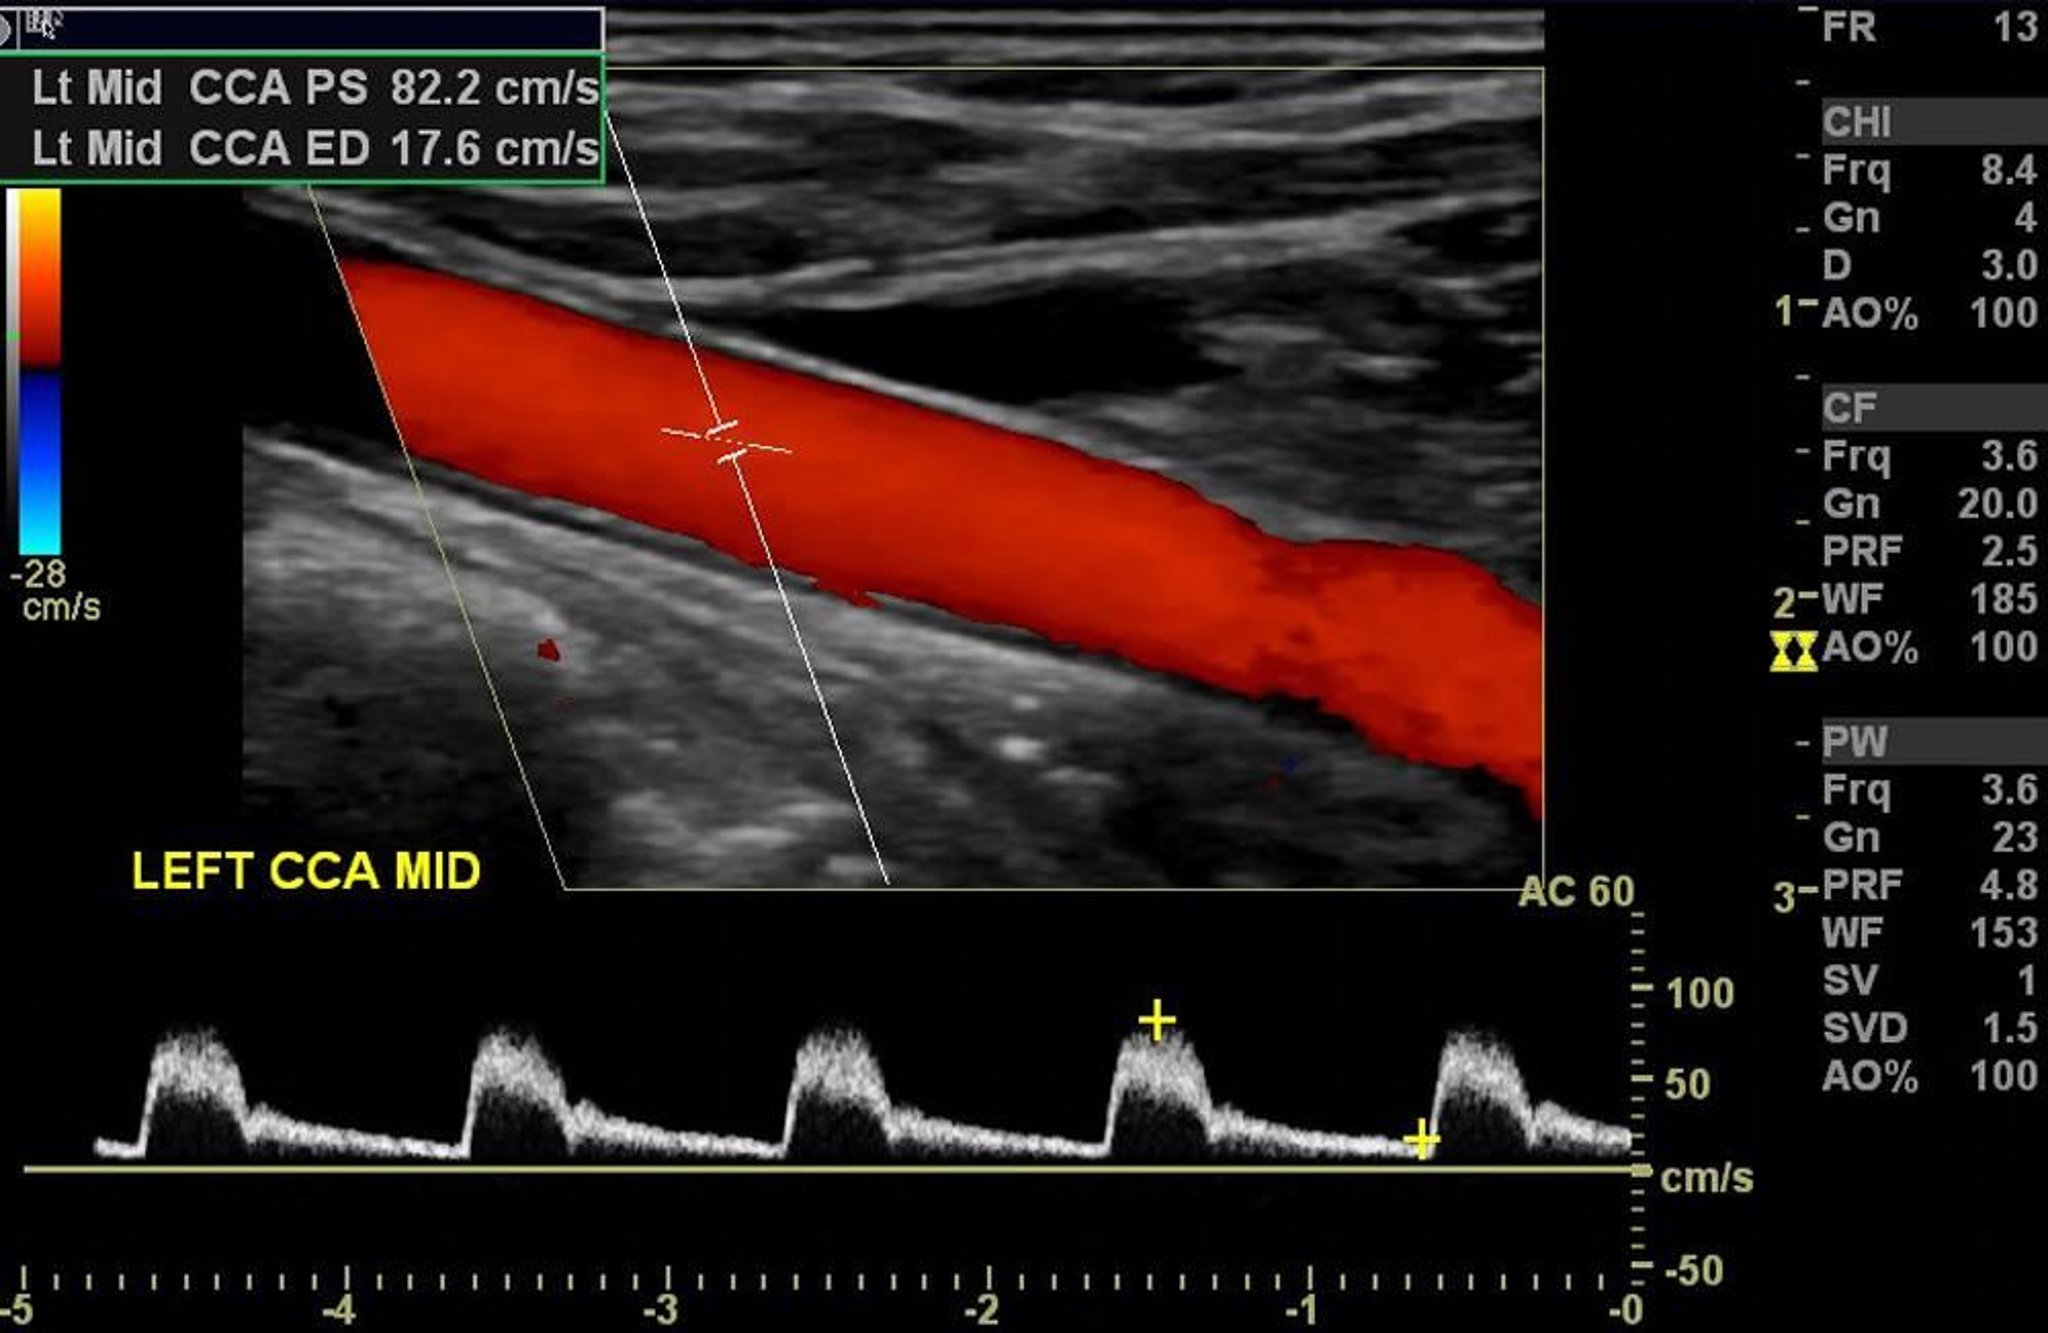

L'échodoppler couleur de l'artère carotide gauche montre un flux artériel normal sans sténose significative.

Image courtoisie de Hakan Ilaslan, MD.